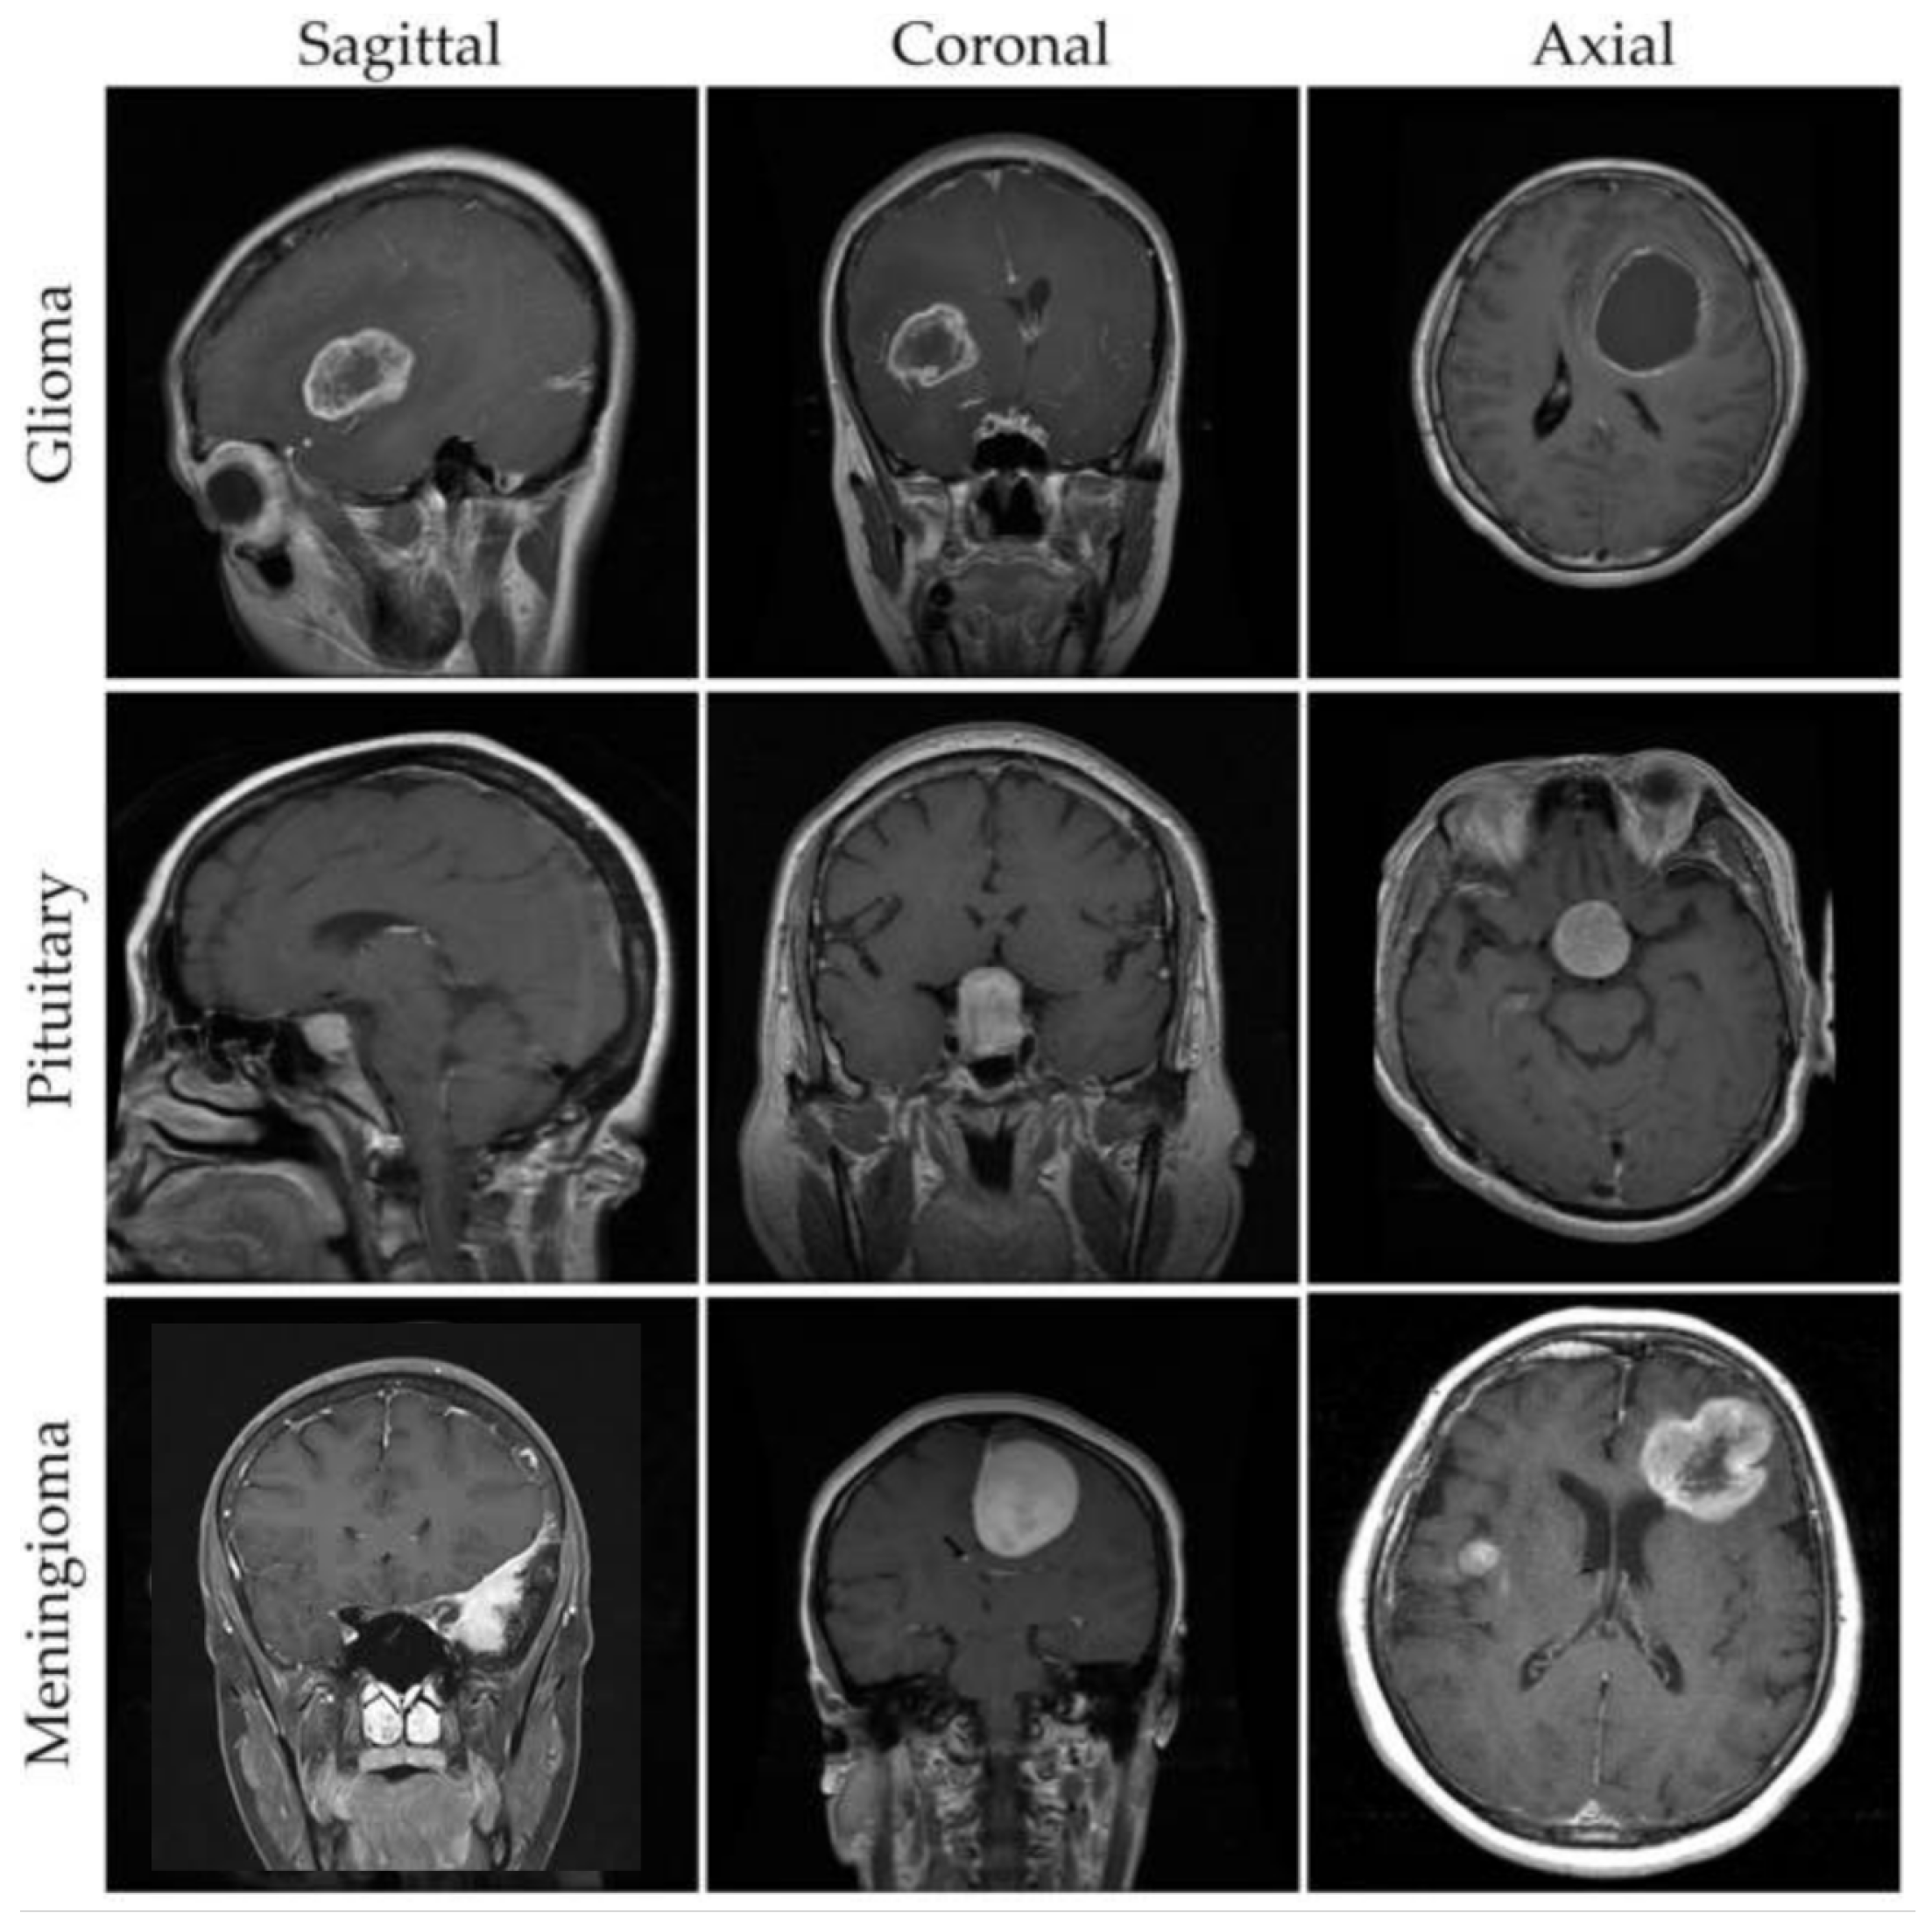

3.2. Dataset Collection and Pre-Processing

- Gliomas and its Symptoms and Causes; Johns Hopkins Medicine: Baltimore, MD, USA, 2022.

- Pituitary Tumors—Symptoms and Causes; Mayo Clinic: Rochester, MN, USA, 2022.

- Meningioma, Risk its Symptoms; Johns Hopkins Medicine: Baltimore, MD, USA, 2022.